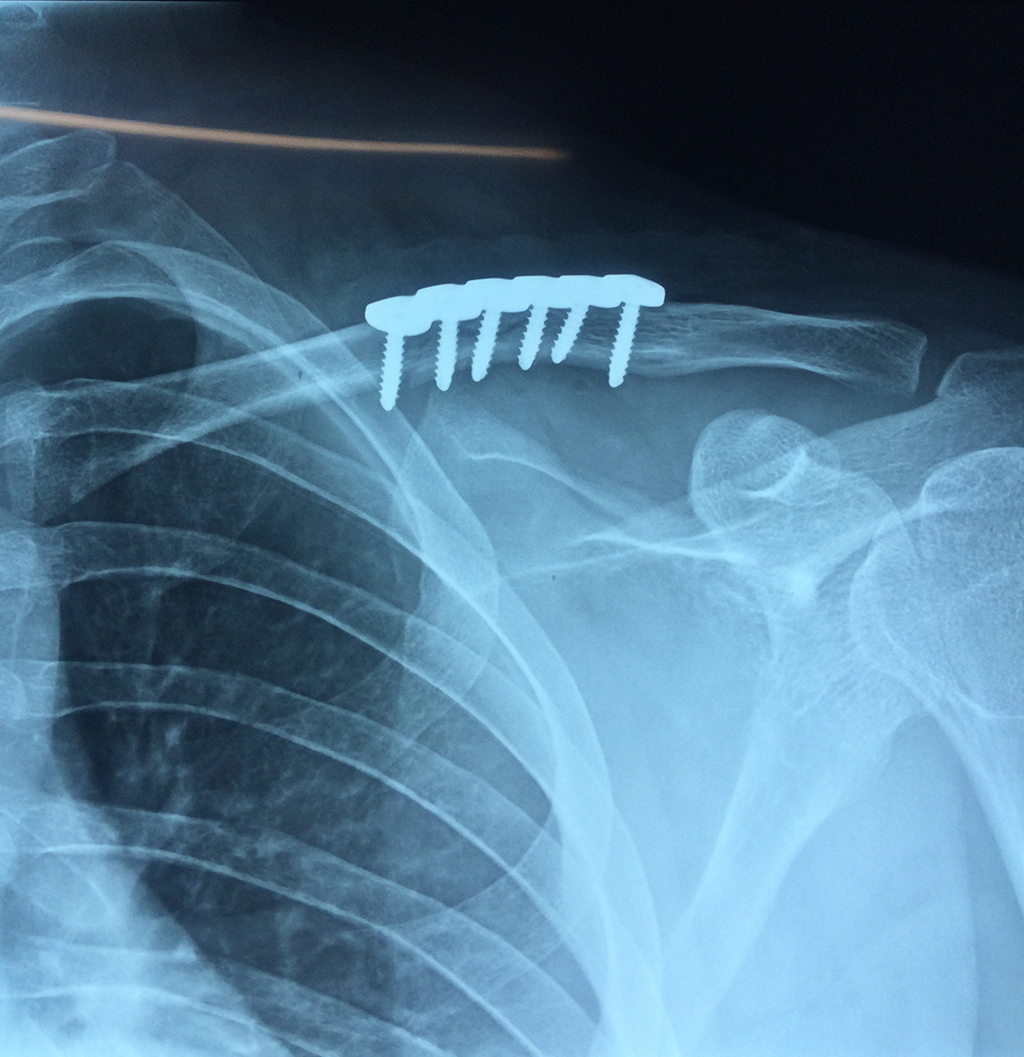

Cirugía de Fémur - Clavícula

La clavícula es un hueso largo, con forma de "S" itálica, situado en la parte anterosuperior del tórax. Junto con la escápula forman la cintura escapular. Se puede palpar por toda su longitud y se extiende del esternón al acromion de la escápula, siguiendo una dirección oblicua lateral y posterior.

Se considera el único medio de unión entre el miembro superior y el tórax. A pesar de su aspecto, similar al de un hueso largo, posee una estructura semejante a la de un hueso plano, ya que carece de epífisis y de diáfisis, lo que la harían entrar dentro de la clasificación de hueso largo. Carece de un canal medular propiamente dicho.